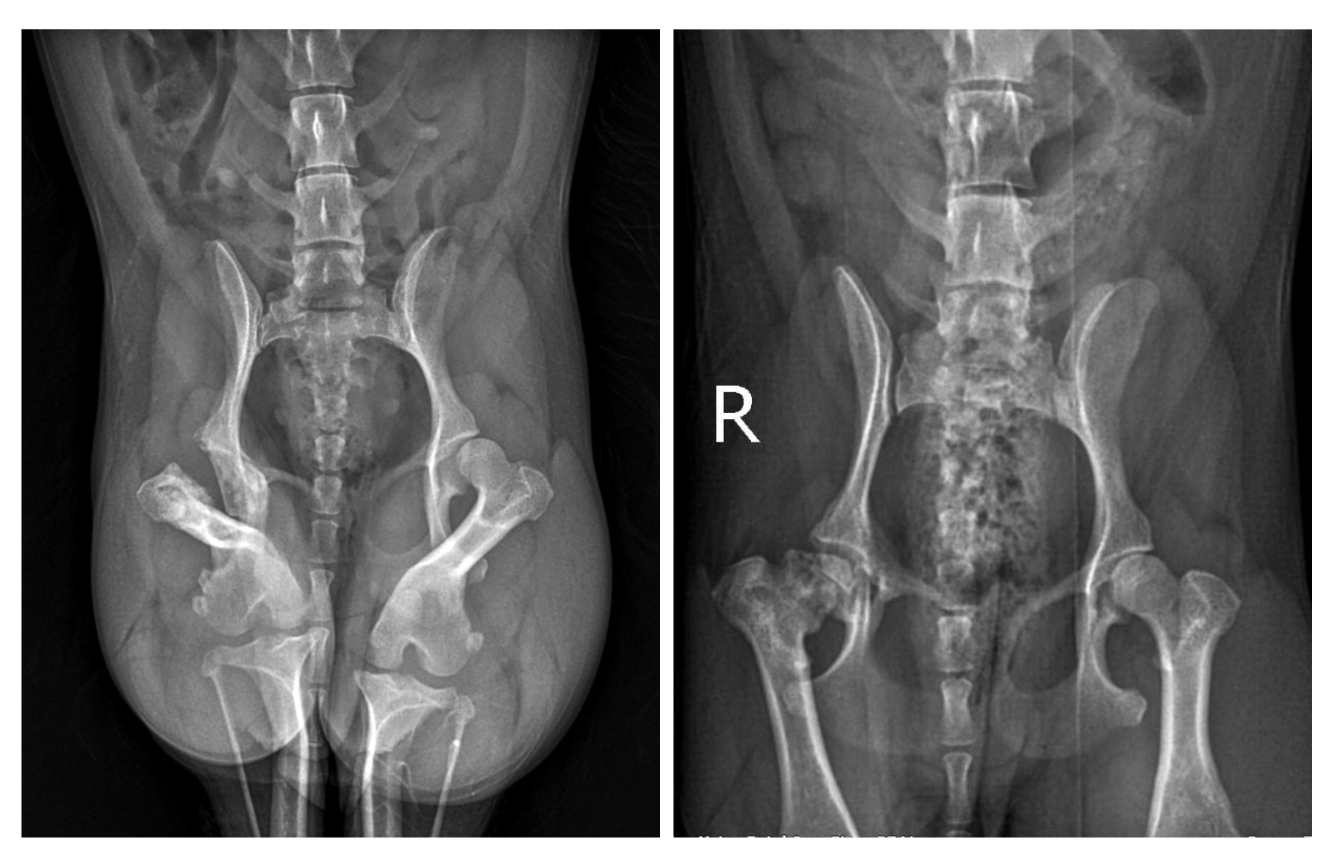

A recent case at Vetco Total Care general practice hospital involved a spayed, 1-year-old year-old Yorkshire Terrier presenting with lameness in the left hind leg. On examination, adduction of the limb provoked a clear response of pain and discomfort. Dr. Robert M. identified the source of discomfort as originating from the coxofemoral joint, leading to diagnostic imaging, including pelvic x-rays. These confirmed our doctor’s suspicion, revealing avascular necrosis of the femoral head — a classic presentation of Legg-Calvé-Perthes disease.

Supported by state-of-the-art imaging diagnostics, the team was able to offer advanced surgical intervention with confidence. In collaboration with the pet parent, Dr. Robert M. performed a femoral head and neck osteotomy (FHO), a procedure that involves the removal of the femoral head to prevent bone-on-bone contact, alleviating pain and restoring movement.